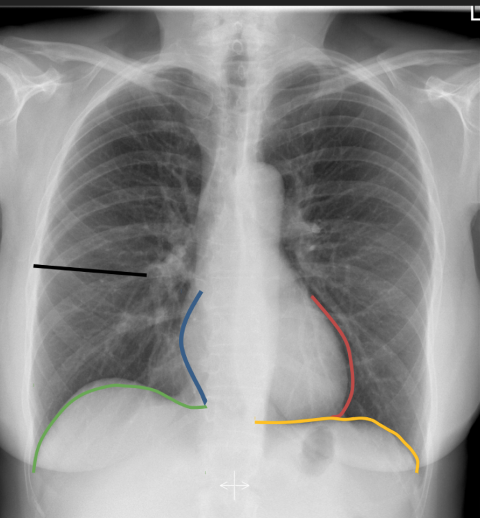

silhouette signs

A

if you lose a key silhouette sign the atelectasis or consolidation is in a specific place

13

Q

lost left hemidiaphragm

atelectasis or consolidation in the left lower lung (LLL)

14

lost right hemidiaphragm

atelectasis or consolidation in the RLL

15

lost right heart border

atelectasis or consolidation in the rright middle lobe

16

lost left heart border

atelectasis or consolidation in the lingula

17

lost upper border of the horizontal fissure

right upper longer